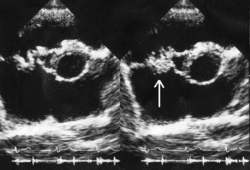

التهاب الشغاف الجرثومي تحت الحاد (بالإنجليزية: Subacute bacterial endocarditis) هو نوع من أنواع التهاب الشغاف (بالتحديد التهاب الشغاف العدوائي).[2] يُمكن أعتبار التهاب الشغاف الجرثومي تحت الحاد نوع من أنواع فرط الحساسية نوع ثلاثة.[3]